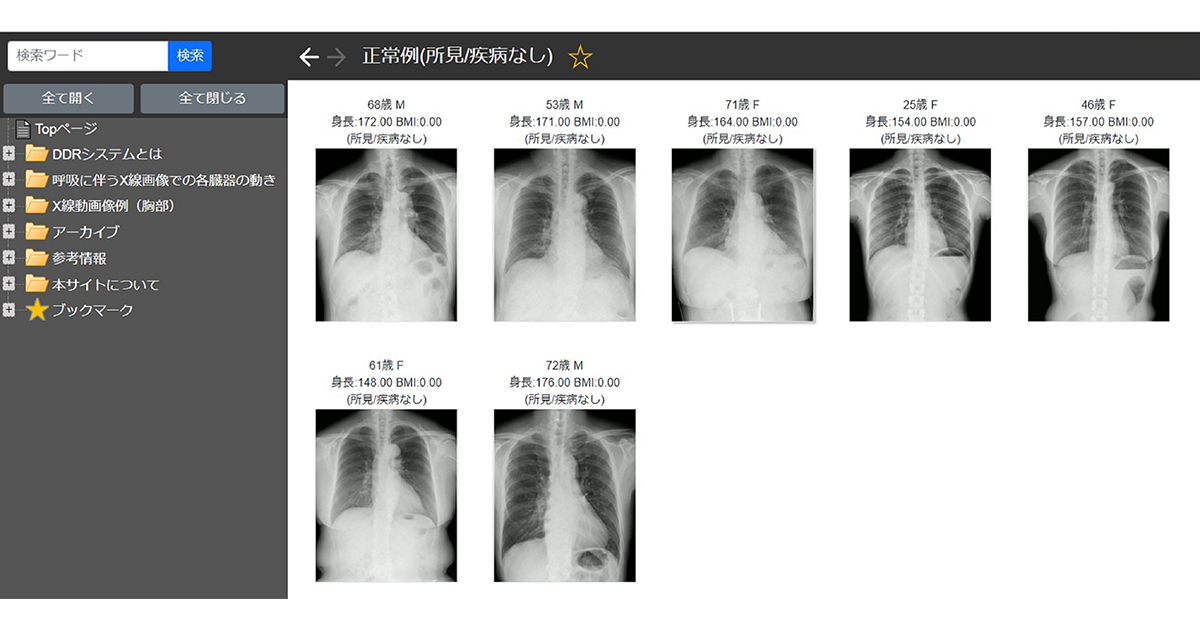

画像解剖に基づく単純X線写真の撮影法と読影のポイント | 黒木。51hv2zpLAYL._AC_SY200_QL15_.jpg。X線撮影装置 | 病院概要 | 沼田脳神経外科循環器科病院。X線撮影法 (診療画像検査法) 医療科学社金森勇雄/著者代表定価 15000円(税別)スレ、傷、折れなど多々あり。)あくまでも中古品の為、気になる方はご遠慮くださいm(_ _)m#診療放射線技師 #放射線技師 #教科書。d-522 X線撮影法大系〈全3巻〉内臓Ⅰ・内臓Ⅱ・頭顎部,幹,四肢。書き込みなし(見落としがあったら申し訳ありません。CPP まとめノート付 問題集 + 模試 2回 予想問題 調達プロフェショナル